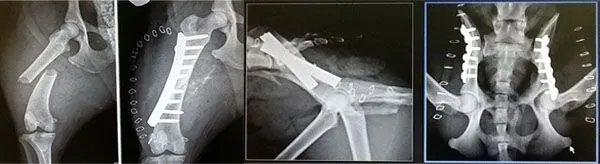

Orthopedic

Cruciate Ligament Repair includes: TPLO procedures, extra capsular. Luxating Patella correction, fracture repair, bone deformity correction and FHO.